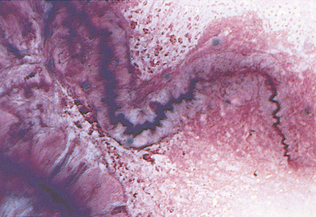

Exudates are fluids with increased cellularity and protein concentration because of inflammation. The following cross-species generalization can be made. Suppurative inflammatory reactions increase the total cell count, the percentage, and the absolute numbers of neutrophils to greater than 85% of the nucleated cells. Suppurative inflammatory reactions usually cause high-normal to elevated total nucleated cell counts, with elevated neutrophil percentages and numerous mesothelial cells and/or macrophages. Mesothelial cells line the body cavities. In the presence of increased fluid within the cavities, these cells may become reactive (i.e., multinucleate, with anisocytosis and anisokaryosis, prominent nucleoli, and basophilic cytoplasm) (Fig. 9-40). Reactive mesothelial cells may be difficult to distinguish from some neoplastic cells. Some mesothelial cells may be present as clusters or rafts of cells. These clusters result from proliferation and exfoliation of cells from the peritoneal lining, or mesothelium, in response to a decrease in contact inhibition between cells on opposing surfaces of the peritoneum, because of the effusion. Macrophages may phagocytize degenerate cells or cellular debris. Migrating parasite larvae can cause increased neutrophil and eosinophil percentages, with or without an elevated total nucleated cell count.

Figure 9-40 A cluster of reactive mesothelial cells. Note the mitotic figure. (From Cowell RL, Tyler RD, and Meinkoth JH: Diagnostic cytology and hematology of the dog and cat, ed 2, St Louis, 1999, Mosby.)